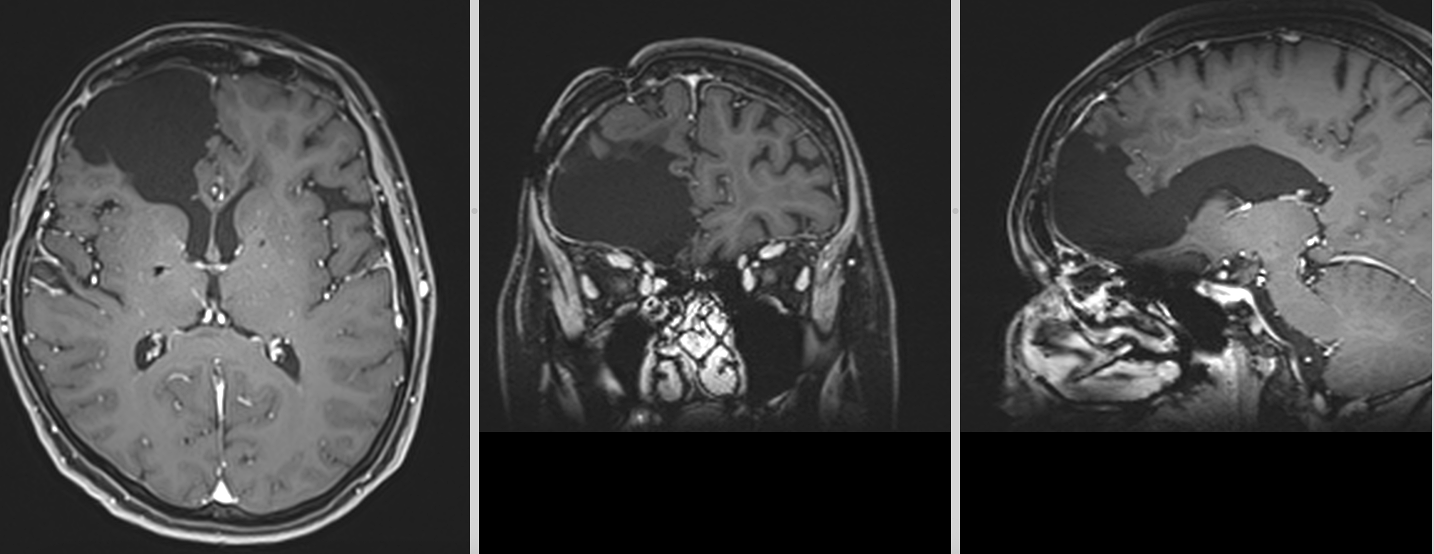

Se reface imagistica – de aceasta dată RMN cerebral cu contrast – și se constată prezența unei tumori cerebrale infiltrative de cca 7/7/6 cm, în cea mai mare parte negadolinofila, hipo-T1, hiper-T2 și FLAIR, cu zone hemoragice la interior și efect de masă important – deplasarea structurilor liniei mediene cu 2 cm, hernie de girus cinguli și hidrocefalie internă prin obstrucția formen Monro – imagine sugestivă pentru un gliom de grad înalt, cel mai probabil glioblastom.

Totuși, la aproximativ 3 ani de la intervenția inițială, RMN-ul cerebral a evidențiat o modificare suspectă la nivelul zonei operate.

Aspectul nu era cel clasic de recidivă agresivă.

Leziunea avea caracteristici mai apropiate de un proces de tip low-grade, cu evoluție lentă și fără semne de agresivitate marcată.